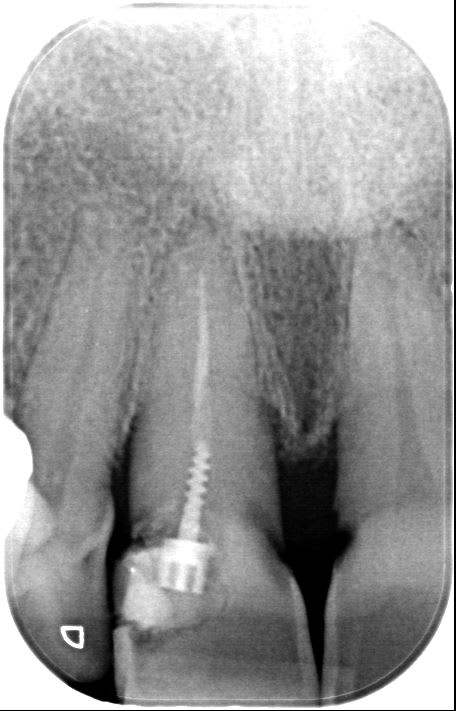

apres c'est la question de l'oeuf et de la poule mais moi je vais pas pleurer sur les dentistes ou les medecins a plus de 7ke par mois pour me recolter a reprendre ca, tous les jours... tous les jours je vois ce genre de ttt:

je vois pas ce qu il y a a revaloriser, en fait c'est deja trop cher pour ce que c'est: